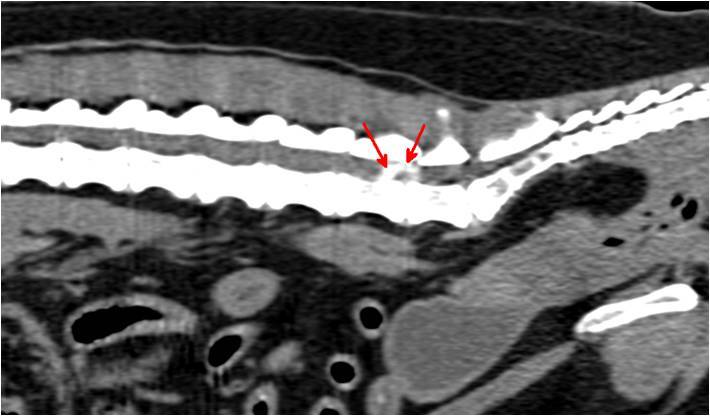

Die vor der Narkose durchgeführte Blutuntersuchung ergab keine Abweichungen von den Normalwerten. Die Röntgenbilder der Knie- und Hüftgelenke waren unauffällig. Bei der seitlichen Aufnahme der Lendenwirbelsäule fiel ein verengter und unruhiger Zwischenwirbelspalt zwischen dem 6. und 7. Lendenwirbel auf (Bild 1). Es wurde der Verdacht auf eine Bandscheibenerkrankung in diesem Bereich geäußert und den Besitzern eine weitere Abklärung mittels Computertomographie empfohlen. In der computertomographischen Untersuchung der Wirbelsäule konnte zwischen dem 6. und 7. Lendenwirbel in den knöchernen Wirbelkanal sowie in das linke Nervenaustrittsloch vorgefallenes Bandscheibenmaterial nachgewiesen werden (Bild 2 und 3). Dieses verursachte eine Kompression des Nervengewebes. Dieser Druck des vorgefallenen Bandscheibenmaterials auf das Nervengewebe war ursächlich für die hochgradige Schmerzhaftigkeit.